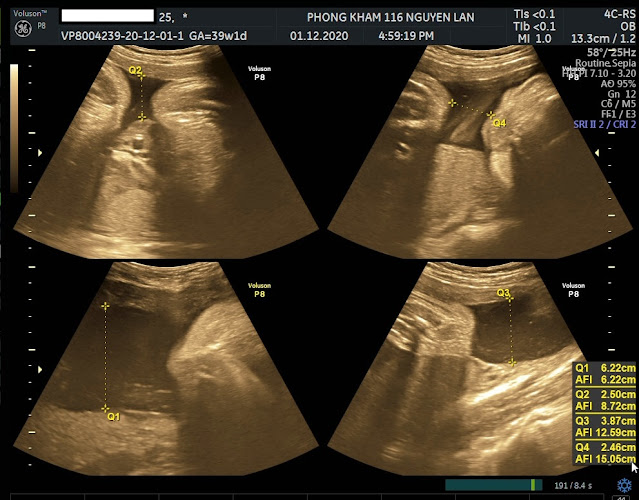

3. Thai 39 tuần có nên đi siêu âm không?

- Những tuần cuối của thai kì mẹ phải đi siêu âm định kỳ

theo lịch hẹn của bác sĩ vì ở những tuần này nước ối và tim thai của bé có thể

có những thay đổi không lường trước, mẹ phải thăm khám thường xuyên: Cân đo huyết

áp, cử động thai, thử nước tiểu, kiểm tra cổ tử cung, đánh giá trọng lượng thai

nhi, nước ối, bánh rau,… Nếu thai bé mẹ

- Ở tuần thai này mẹ hãy nhớ chỉ siêu âm 2D thôi ạ, mặc dù

chưa có dẫn chứng nào chứng minh siêu âm có hại cho thai nhi nhưng mình chỉ nên

làm siêu âm 4D, 5D 3 mốc quan trọng trong thai kì đó là 12, 22 và 32 thôi nhé.